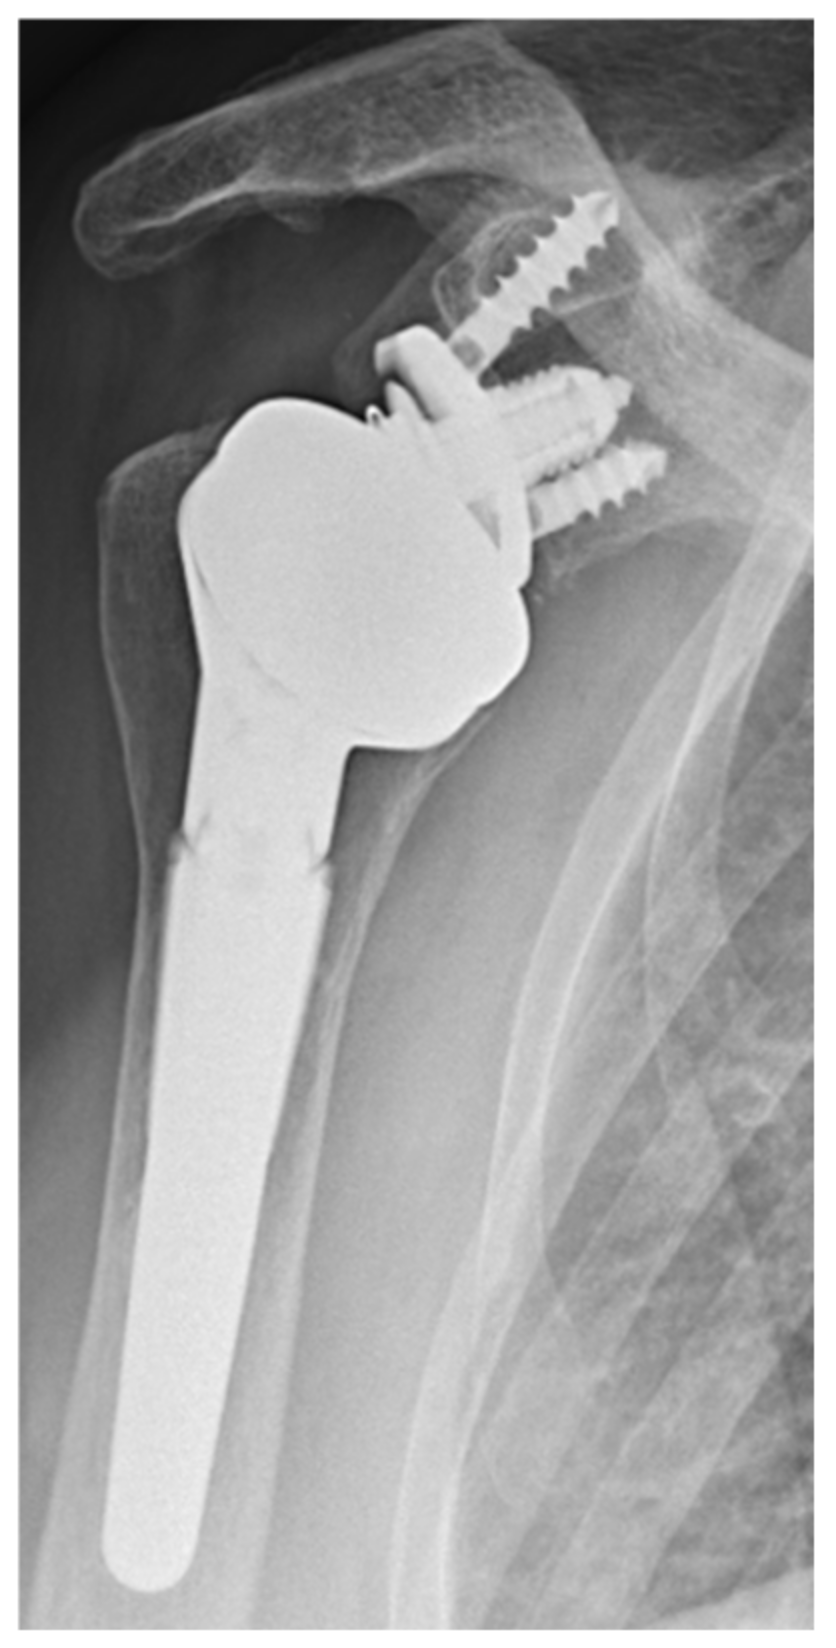

All the patients received both a general anesthetic and an interscalene block. The operation was performed in beach chair position, through a deltopectoral approach. The SMR RSA (LimaCorporate S.p.A, 33038 Villanova di San Daniele del Friuli, Udine, Italy) with the HP glenosphere was implanted in all the cases (Figure 2).

Figure 2. SMR reverse HP glenosphere (LimaCorporate S.p.A, 33038 Villanova di San Daniele del Friuli, Udine, Italy).

Further studies are needed in order to analyze the notching evolution with IB-RSA at longer follow-up and verify if the notching remains mainly mechanical, or if the osteolysis will spread over the screw reaching the central peg, with a potential risk of loosening [12]. Moreover, histological studies on retrieved implants will be useful to clarify this phenomenon in vivo. In contrast with other authors [8,16], we did not find a statistical difference in baseplate inclination between patients with and without notching in our series. This finding may have different explanations. First, the limited number of patients included in this series compared to other series [8,16]. Second, the design of the glenosphere presenting an inferior extension may compensate for a slight superior inclination of the baseplate (Figure 2). Third, we believe that scapular notching is more linked to the inclination of the baseplate relative to the scapular neck [11] or to the intrinsic neck morphology [3] compared to the inclination relative to the supraspintus fossa.

Regarding complications, only one patient was revised because of an infection and two patients had an acromial fracture. The reported rate of acromial fracture with classic reverse design is generally lower [1,36], but due to the low number of patients included in this series, it is impossible to evaluate whether increasing the glenosphere diameter could be associated with a higher risk of acromial fracture. However, Kohut et al. [27], in a larger series comparing 40/44 mm with 36 mm glenosphere, did not report an increased risk of acromial fracture. One important phenomenon that we observed in three cases is an initial glenoid migration, which stabilized within the first year and remains in a high and severe superiorly tilted baseplate (Figure 2). We noticed that in all these cases, the superior part of the glenoid was not perfectly in contact with the subchondral bone, probably due to an incorrect technique and uncompleted cartilage removal. Based on this observation, we recommended a good preparation of the subchondral bone in order to match the baseplate profile.